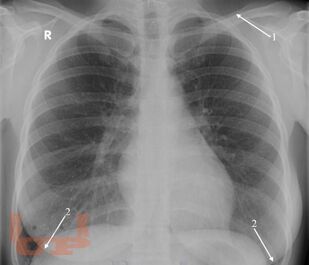

Рентгеноанатомия органов грудной клетки

В данном электронном пособии систематизированы и подробно изложены сведения о рентгеновской анатомии органов грудной клетки.